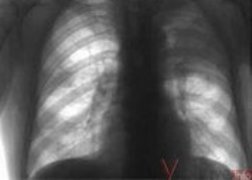

Своевременное обращение дает дополнительные гарантии, что туберкулез вылечат.

– По критериям ВОЗ в 1995 году зарегистрировано эпидемию туберкулеза, – рассказал Виктор Лысак, начальник Главного управления здравоохранения ОГА. – По уровню заболеваемости наше государство занимает седьмое место в Европе. Масштаб распространенности туберкулеза превратил эту опасную болезнь не просто в эпидемию, а в важную социальную проблему. Полтавская область занимает 5 место по заболеваемости туберкулезом в Украине среди областей с самой низкой заболеваемостью. Туберкулез можно вылечить. Одно из условий – своевременное обращение к врачу за медицинской помощью и соблюдение лечения в случае заболеваемости.